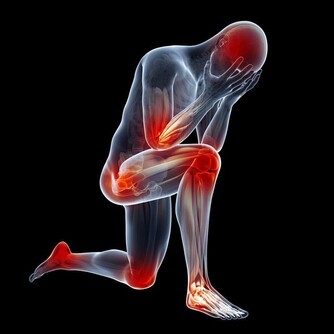

但最近卻一連發現有3位患者,在進行到第4個療程的時候,出現了不同程度的腎功能受損。

當然,我們首先想到的是順鉑對腎臟的損傷,但這幾個病人的腎臟代償能力怎麼就這麼差呢?

帶著這個問題,我在隨訪中對這幾個病人的飲食習慣問了一下,發現她們的確都和我一樣,喜歡吃蘑菇。